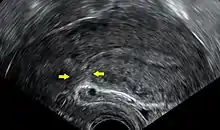

![]() فَريق من أطباء التوليد يعملون على إجراء ولادة قيصرية في مُستشفى حديث. تُظهر الصُورة اللحظة الأولى التي تَلمح الأم فيها مولودها. | |